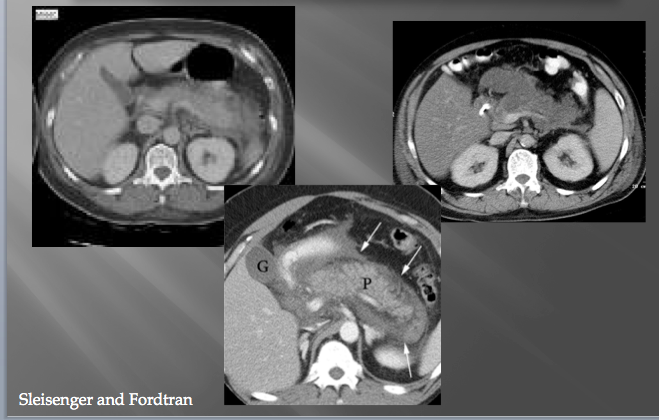

pancreatic pseudocyst